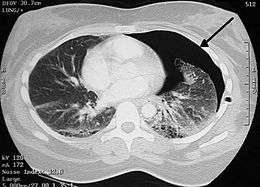

| Coronal CT scan showing lucencies (pale areas in radiography) in the lung caused by pulmonary lacerations on the left of the image (black arrows) | |

Pulmonary laceration may not be visible using chest X-ray because an associated pulmonary contusion or hemorrhage may mask it.[1][9] As the lung contusion clears (usually within two to four days), lacerations begin to become visible on chest X-ray.[3] CT scanning is more sensitive and better at detecting pulmonary laceration than X-rays are,[1][4][14][17] and often reveals multiple lacerations in cases where chest X-ray showed only a contusion.[14] Before CT scanning was widely available, pulmonary laceration was considered unusual because it was not common to find with X-ray alone.[14] On a CT scan, pulmonary lacerations show up in a contused area of the lung,[9] typically appearing as cavities filled with air or fluid[18] that usually have a round or ovoid shape due to the lung's elasticity.[6]

Hematomas appear on chest radiographs as smooth masses that are round or ovoid in shape.[1] Like lacerations, hematomas may initially be hidden on X-ray by lung contusions, but they become more apparent as the contusion begins to heal.[1] Pneumatoceles have a similar shape to that of hematomas but have thin, smooth walls.[19] Lacerations may be filled completely with blood, completely with air, or partially with both.[6] Lacerations filled with both blood and air display a distinctive air-fluid level.[6] A single laceration may occur by itself, or many may be present, creating an appearance like Swiss cheese in the radiography of the lung.[6]